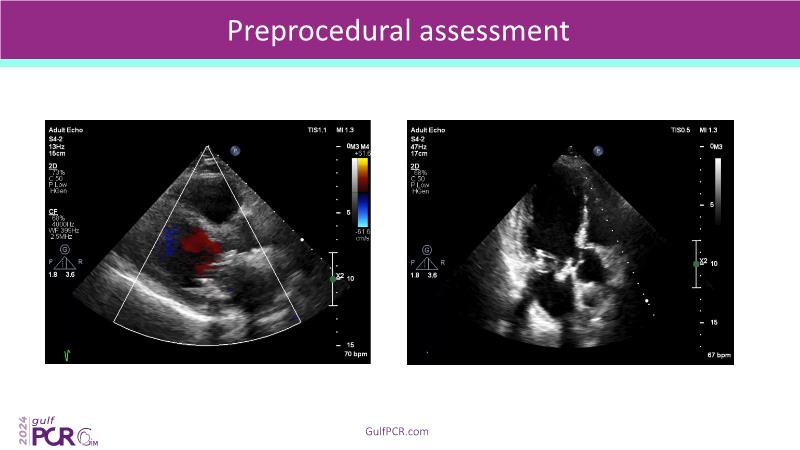

Stay ahead in TAVI innovation by exploring the advanced balloon-expandable Myval THV series. This session highlights the latest clinical data, optimal sizing and implantation techniques, and valuable real-world insights, including long-term follow-up results.

- To understand the best practices for Myval sizing and implantation technique for best outcomes